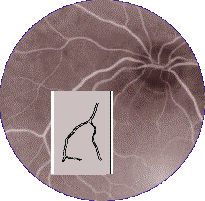

La Dra. María Elena Martínez de la Universidad Autónoma de México (UNAM) y el Dr. Arturo Espinoza de nuestro cuerpo académico, justamente están estudiando el comportamiento de la venas que circundan e irrigan la retina, por medio del procesamiento de la información podrían determinar anomalías funcionales que deterioran la visión, por medio del diagnóstico de patologías como el glaucoma, retinitis, presión intraocular y macular, etc.